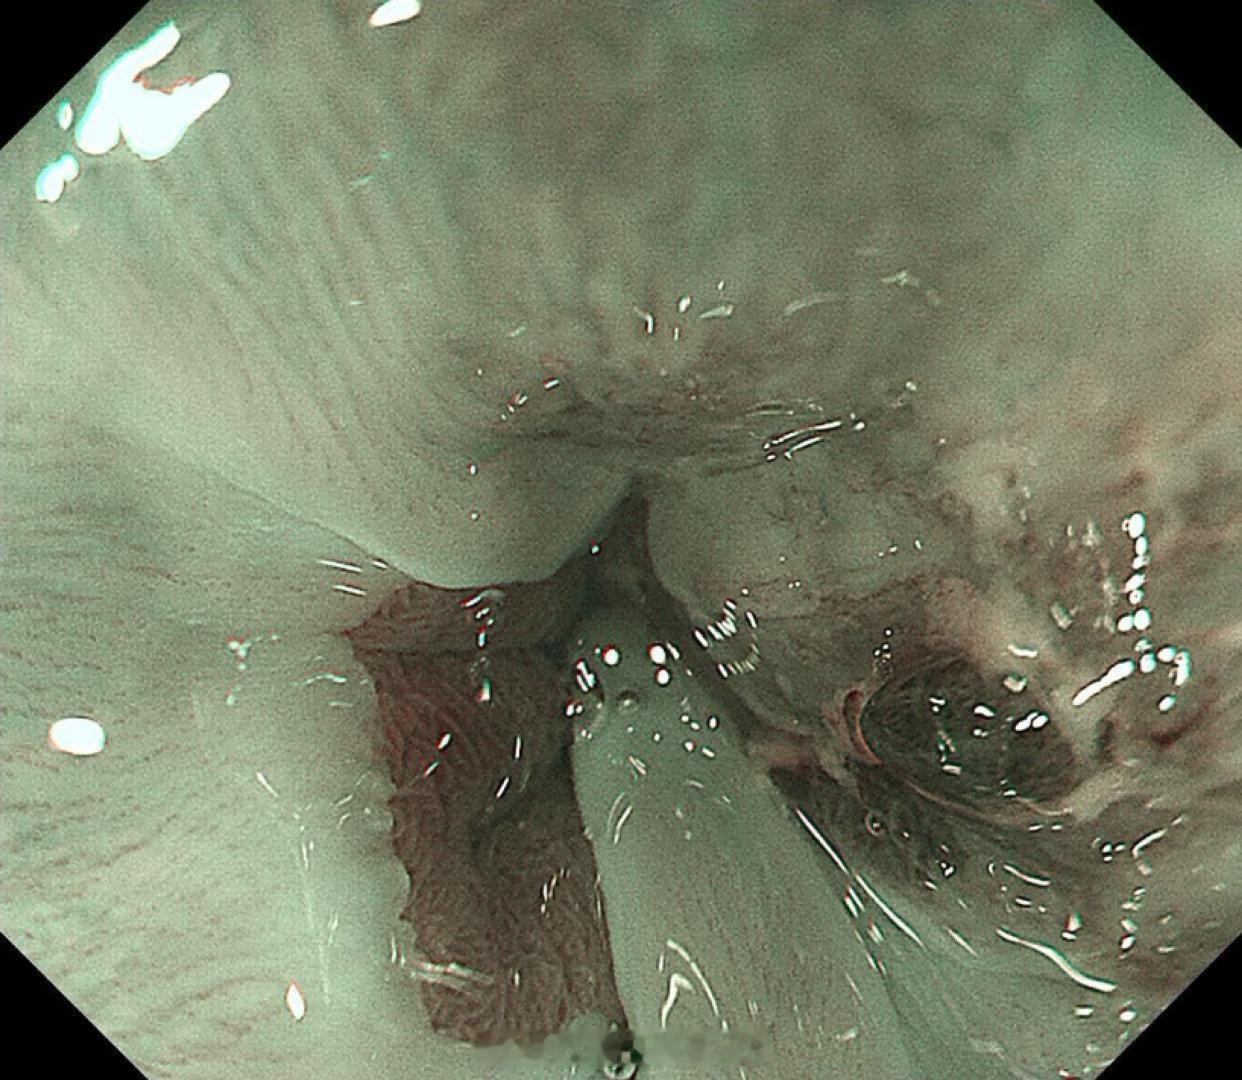

这是个兄弟医院做的内镜发现有贲门病灶,老人体型腹型肥胖很典型,返流持续那么多年导致的Barrett食管癌风险肯定是最高的,她女婿找我精查会诊了一次,我看着病灶虽小,但是有点僵硬,感觉已经到了黏膜下的barrett食管癌,但是他们都想尝试切除看看浸润深度,诊断性esd实施后黏膜下550微米,一般来说这地方超过500微米已经是sm2,淋巴结转移风险急剧加大了,后面就要纠结要不要追加外科手术,但是这个手术做了生活质量会相当不好。所以这种癌的最好措施是预防,发现非常困难,往往一发现就是深了。腹型肥胖的人群减重以减少返流是很重要的。